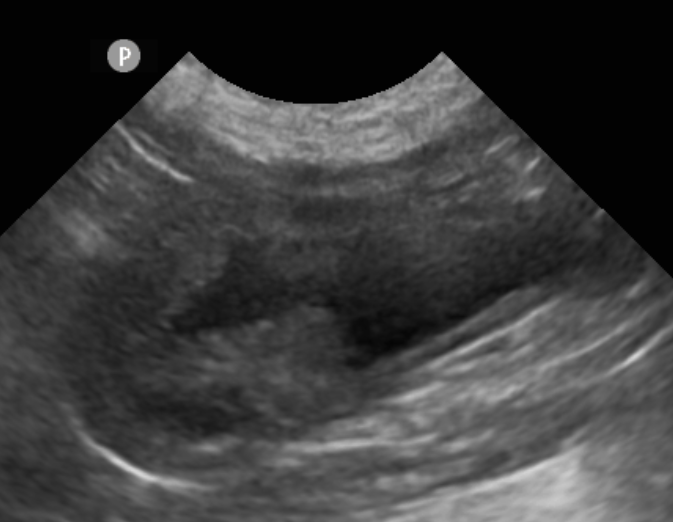

妞妞(化名)是一隻8歲絕育柯基母犬,就診的一年前因為血尿在他院發現有膀胱團塊。

因此,本院選擇用無創內視鏡,直接從尿道進入膀胱採樣,術後當天可以直接回家,不用傷口照護

採樣結果確診為惡性程度較低的尿路上皮細胞癌